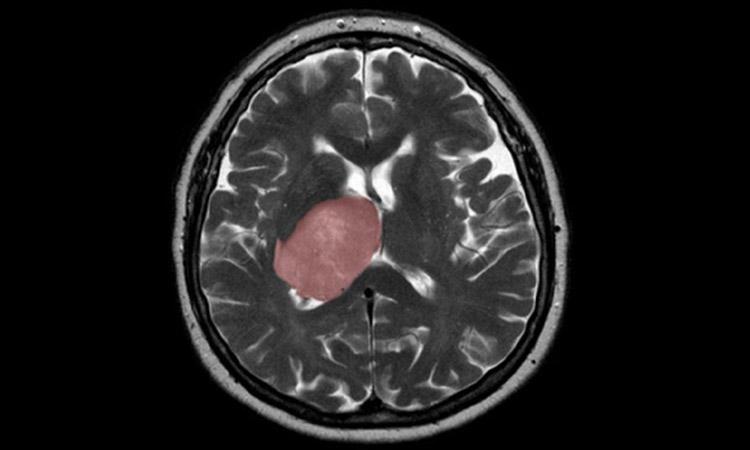

If you eat undercooked meat then you may need to stop it, as researchers have found a link between Toxoplasma gondii (T. gondii) infection and the risk of glioma, a rare type of brain cancer, in adults.

T. gondii is a common parasite that is most commonly acquired from undercooked meat and may lead to the formation of cysts in the brain.

The study, published in the International Journal of Cancer, suggests that people who have glioma are more likely to have antibodies to T. gondii (indicating that they have had a previous infection) than a similar group that is cancer-free.

Although glioma is a relatively rare disease, it is a highly fatal cancer. Globally in 2018, there were an estimated 300,000 incident cases and 241,000 deaths due to brain and other nervous system cancers, the researchers said.

The majority (80 per cent) of malignant brain tumours are gliomas, for which the estimated five-year relative survival rate is a stark 5 per cent, they added.